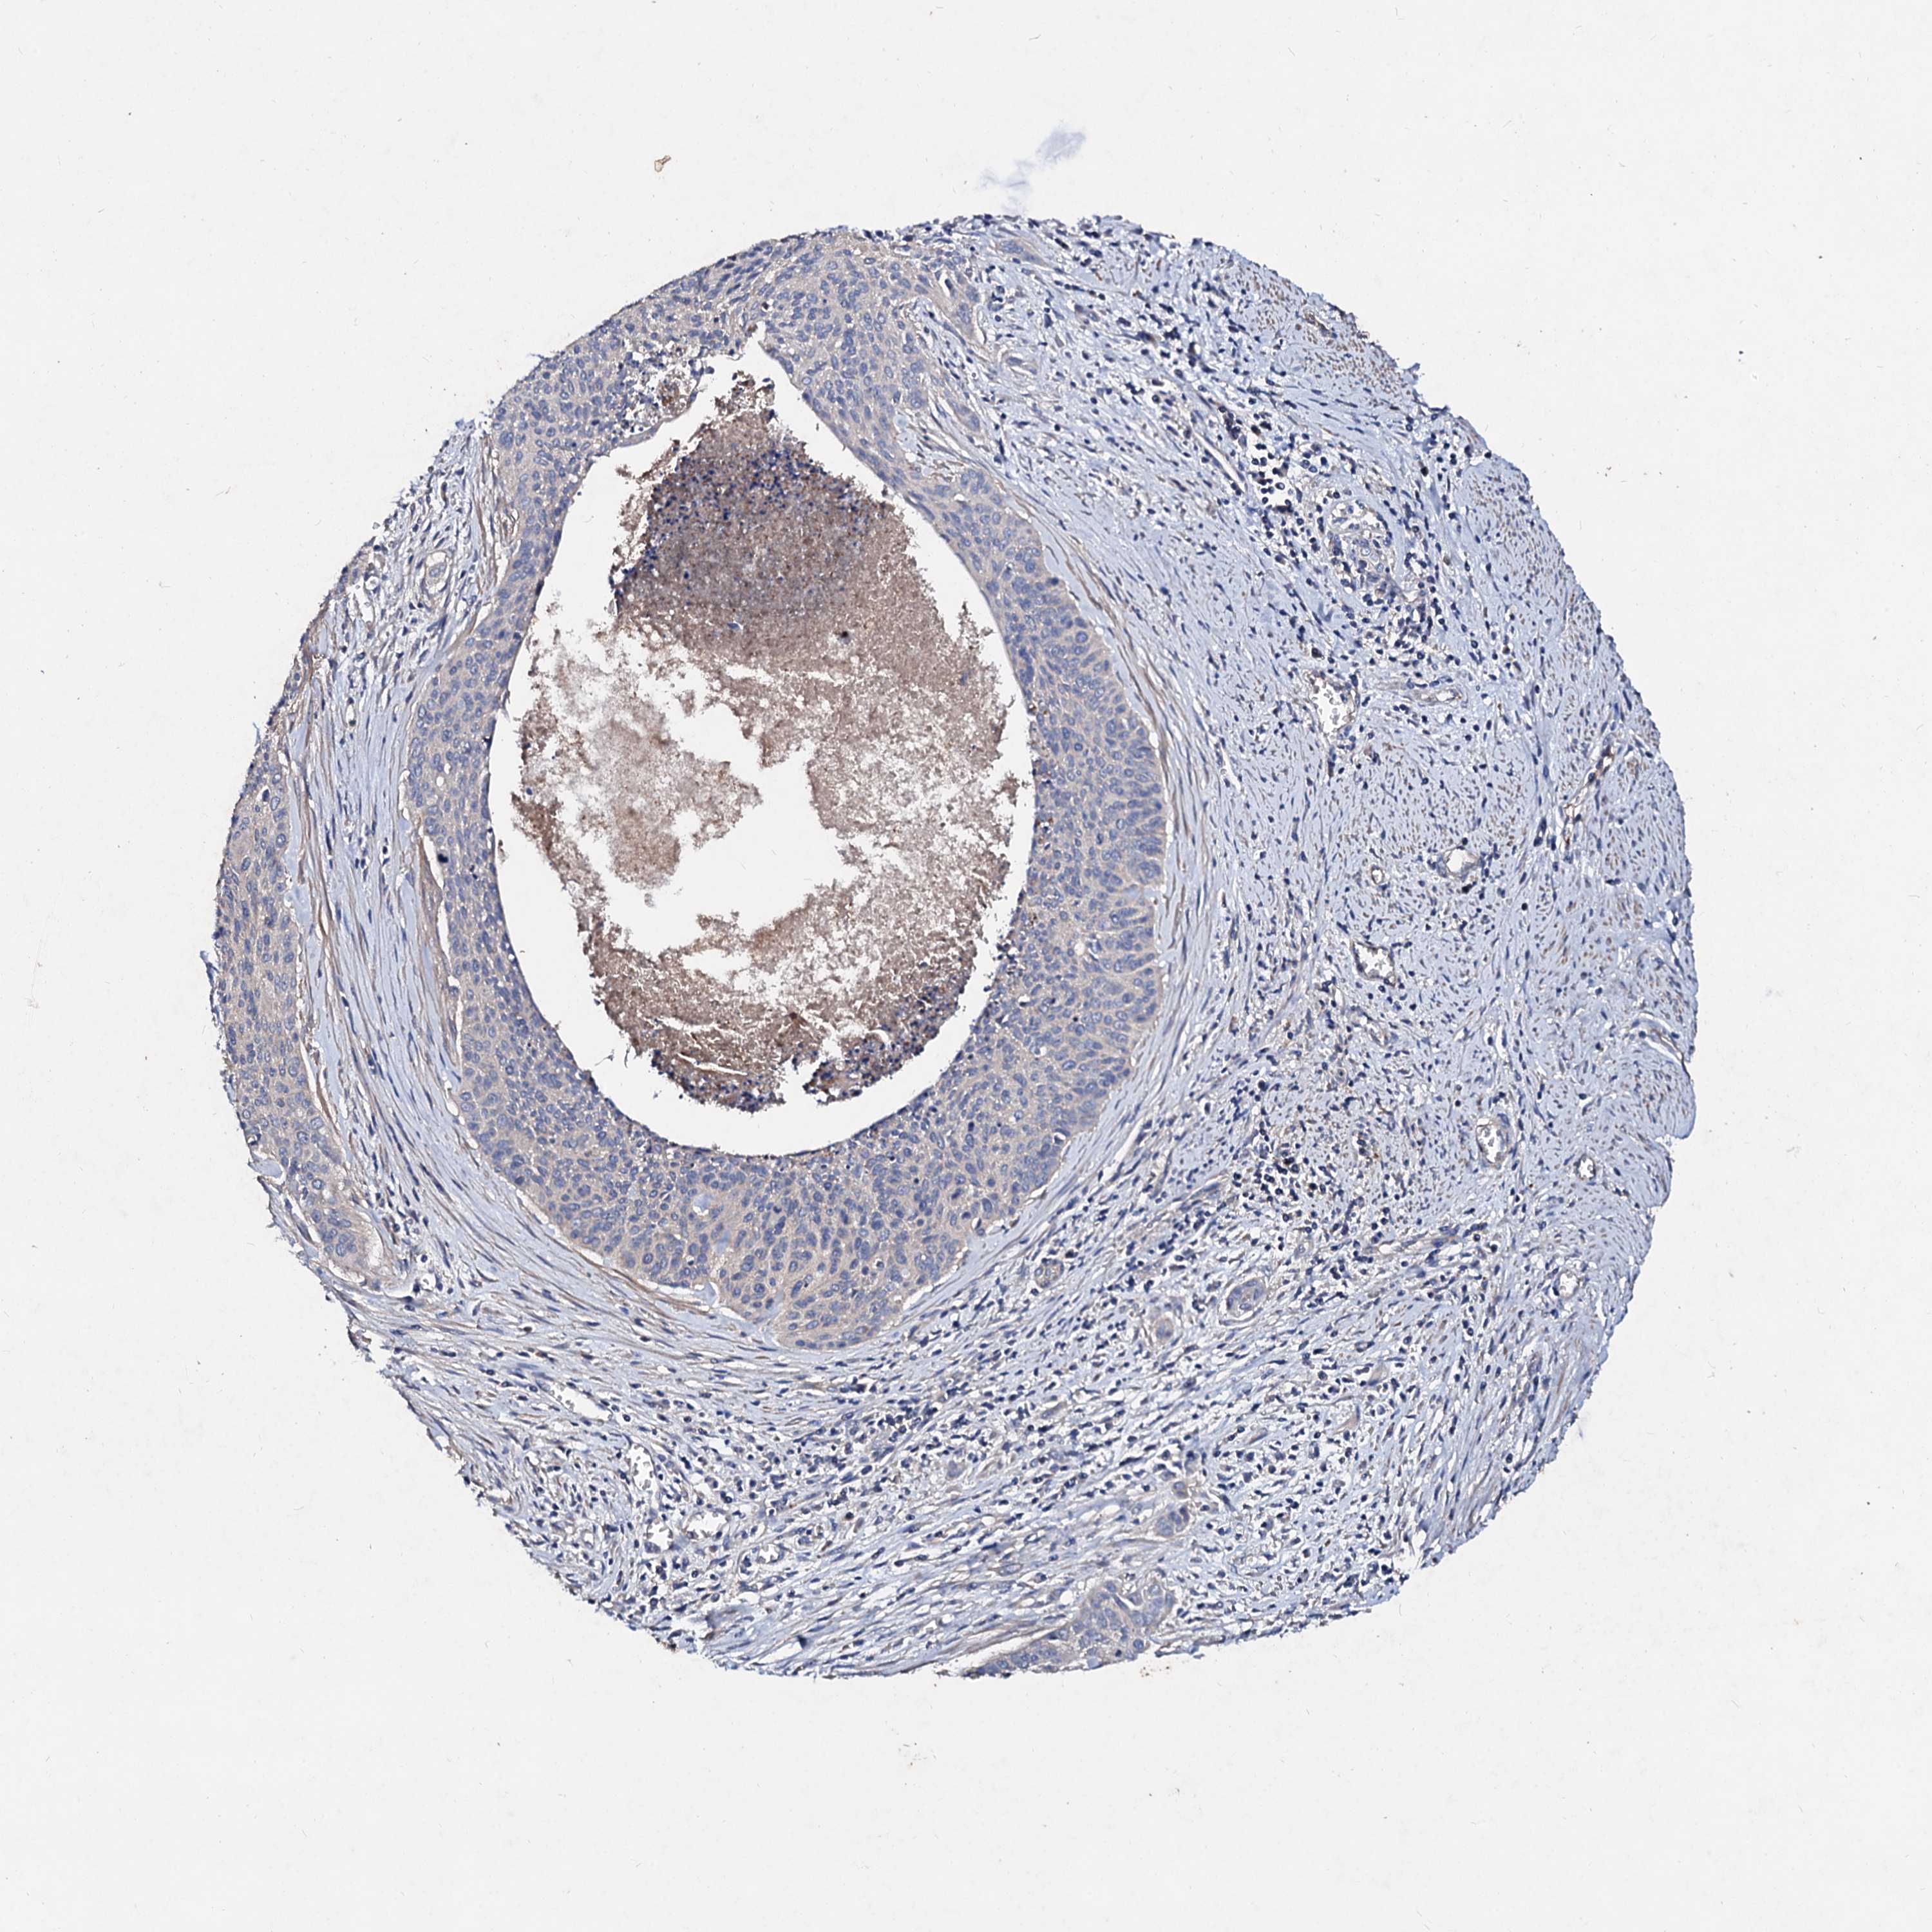

CERVICAL CANCER - Protein expressioni

A mouse-over function shows sample information and annotation data. Click on an image to view it in a full screen mode. Samples can be filtered based on level of antibody staining by selecting one or several of the following categories: high, medium, low and not detected. The assay and annotation is described here.

Note that samples used for immunohistochemistry by the Human Protein Atlas do not correspond to samples in the TCGA dataset.

Antibody stainingi

Antibody staining in the annotated cell types in the current human tissue is reported as not detected, low, medium, or high, based on conventional immunohistochemistry profiling in selected tissues. This score is based on the combination of the staining intensity and fraction of stained cells.

Each image is clickable and will lead to virtual microscopy that enables deeper exploration of all samples and also displays staining intensity scores, fraction scores and subcellular localization as well as patient and tissue information for each sample.

Antibody HPA040120

Staining

High

Medium

Low

Not detected

Intensity

Strong

Moderate

Weak

Negative

Quantity

>75%

75%-25%

<25%

None

Location

Nuclear

Cytoplasmic/membranous

Cytoplasmic/membranous,nuclear

Squamous cell carcinoma, NOS